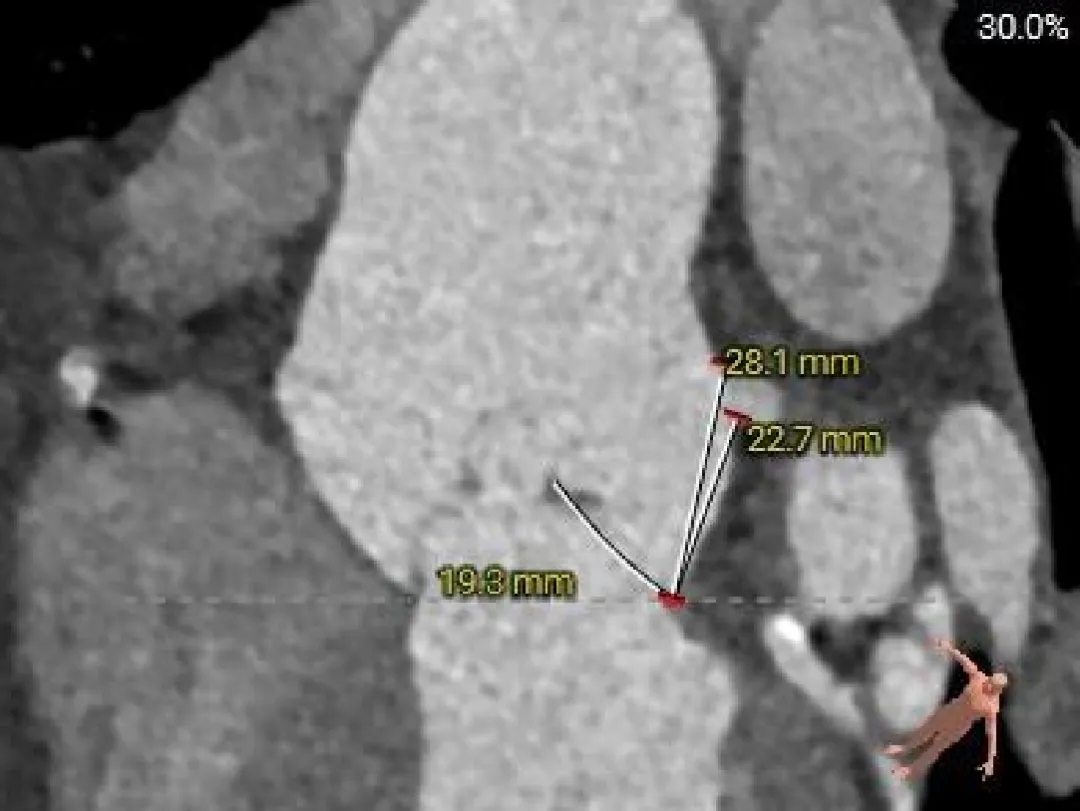

术前CT分析

主动脉根部测量

Annulus-收缩期

30.3mm

Annulus-舒张期

29.9mm

LVOT

30.8mm

sinus

STJ

46.1mm

AAO

53.7mm

瓣上结构测量

瓣上 2mm

瓣上 4mm

30.2mm

瓣上 6mm

瓣上 8mm

29.5mm